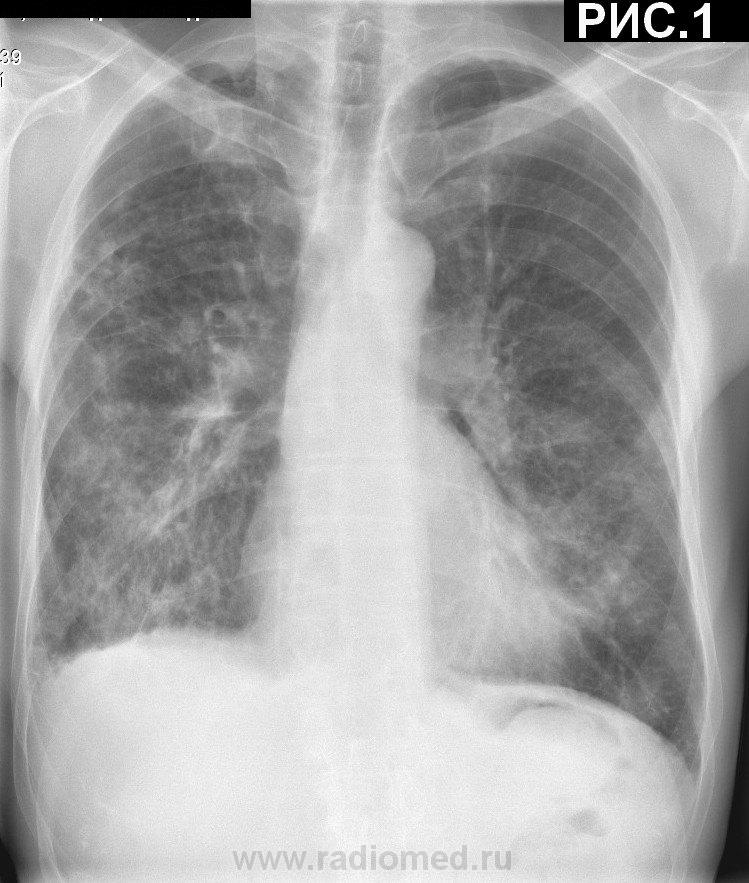

Пациент 74 г. Поступил с диагнозом ИБС: мерцательная аритмия...Инженер. Профанамнеза нет. Туберкулезом не болел. Неднократно последние 10 лет обследовался в ПТД. МБТ (-). Жалобы на одышку при физической нагрузке. Кашль, мокрота отсутствуют. Температура тела нормальная. Кровь: лейк.7,6*109/л, Эр.3,9, Нв-131г/л, НСТ-38%, Тромб.213, п-я.2%, сег.52%, лим.35%, м.8%. СОЭ-40 мм/ч. Рентгенограммы  грудной клетки (рис.1, рис.2) от 30.5.11. КТ  грудной клетки от 23.10.2010 г. см. ниже в комментариях. С уважением Nikolas

К метатуберкулёзным изменениям отнёс бы плевроапикальные наложения. Возможно, в верхушках есть и мелкие очаги, но разрешение репродукций… не очень.

Всё остальное – признаки хронического неспецифического. Бронхоэктазы в базальных сегментах весьма вероятны, особенно справа, но опять же, недостаточно видна структура лёгочного рисунка. Это фон. На этом фоне в верхней доле правого легкого, по-видимому, есть пневмония, и в нижней не исключается. Сердце не лёгочное. Плевродиафрагмальные спайки справа.

Вроде бы угадывается какая-то диссеминация, но для такого заключения нужны полноценные изображения.

В средних и нижних отделах обоих лёгочных полей (больше справа) лёгочный рисунок усилен и деформирован по сетчатому типу, справа на этом фоне не исключается наличие инфильтрации нижней доли (ну или снижение прозрачности, возникает большое желание написать по типу "матового стекла) Плотные линейные тени пневмофиброза. Плеврофиброзные изменения.

Распространённые пневмо, плеврофиброзные изменения. Не исключается н/долевая пневмония справа (диф DS с интерстициальным пневмонитом).